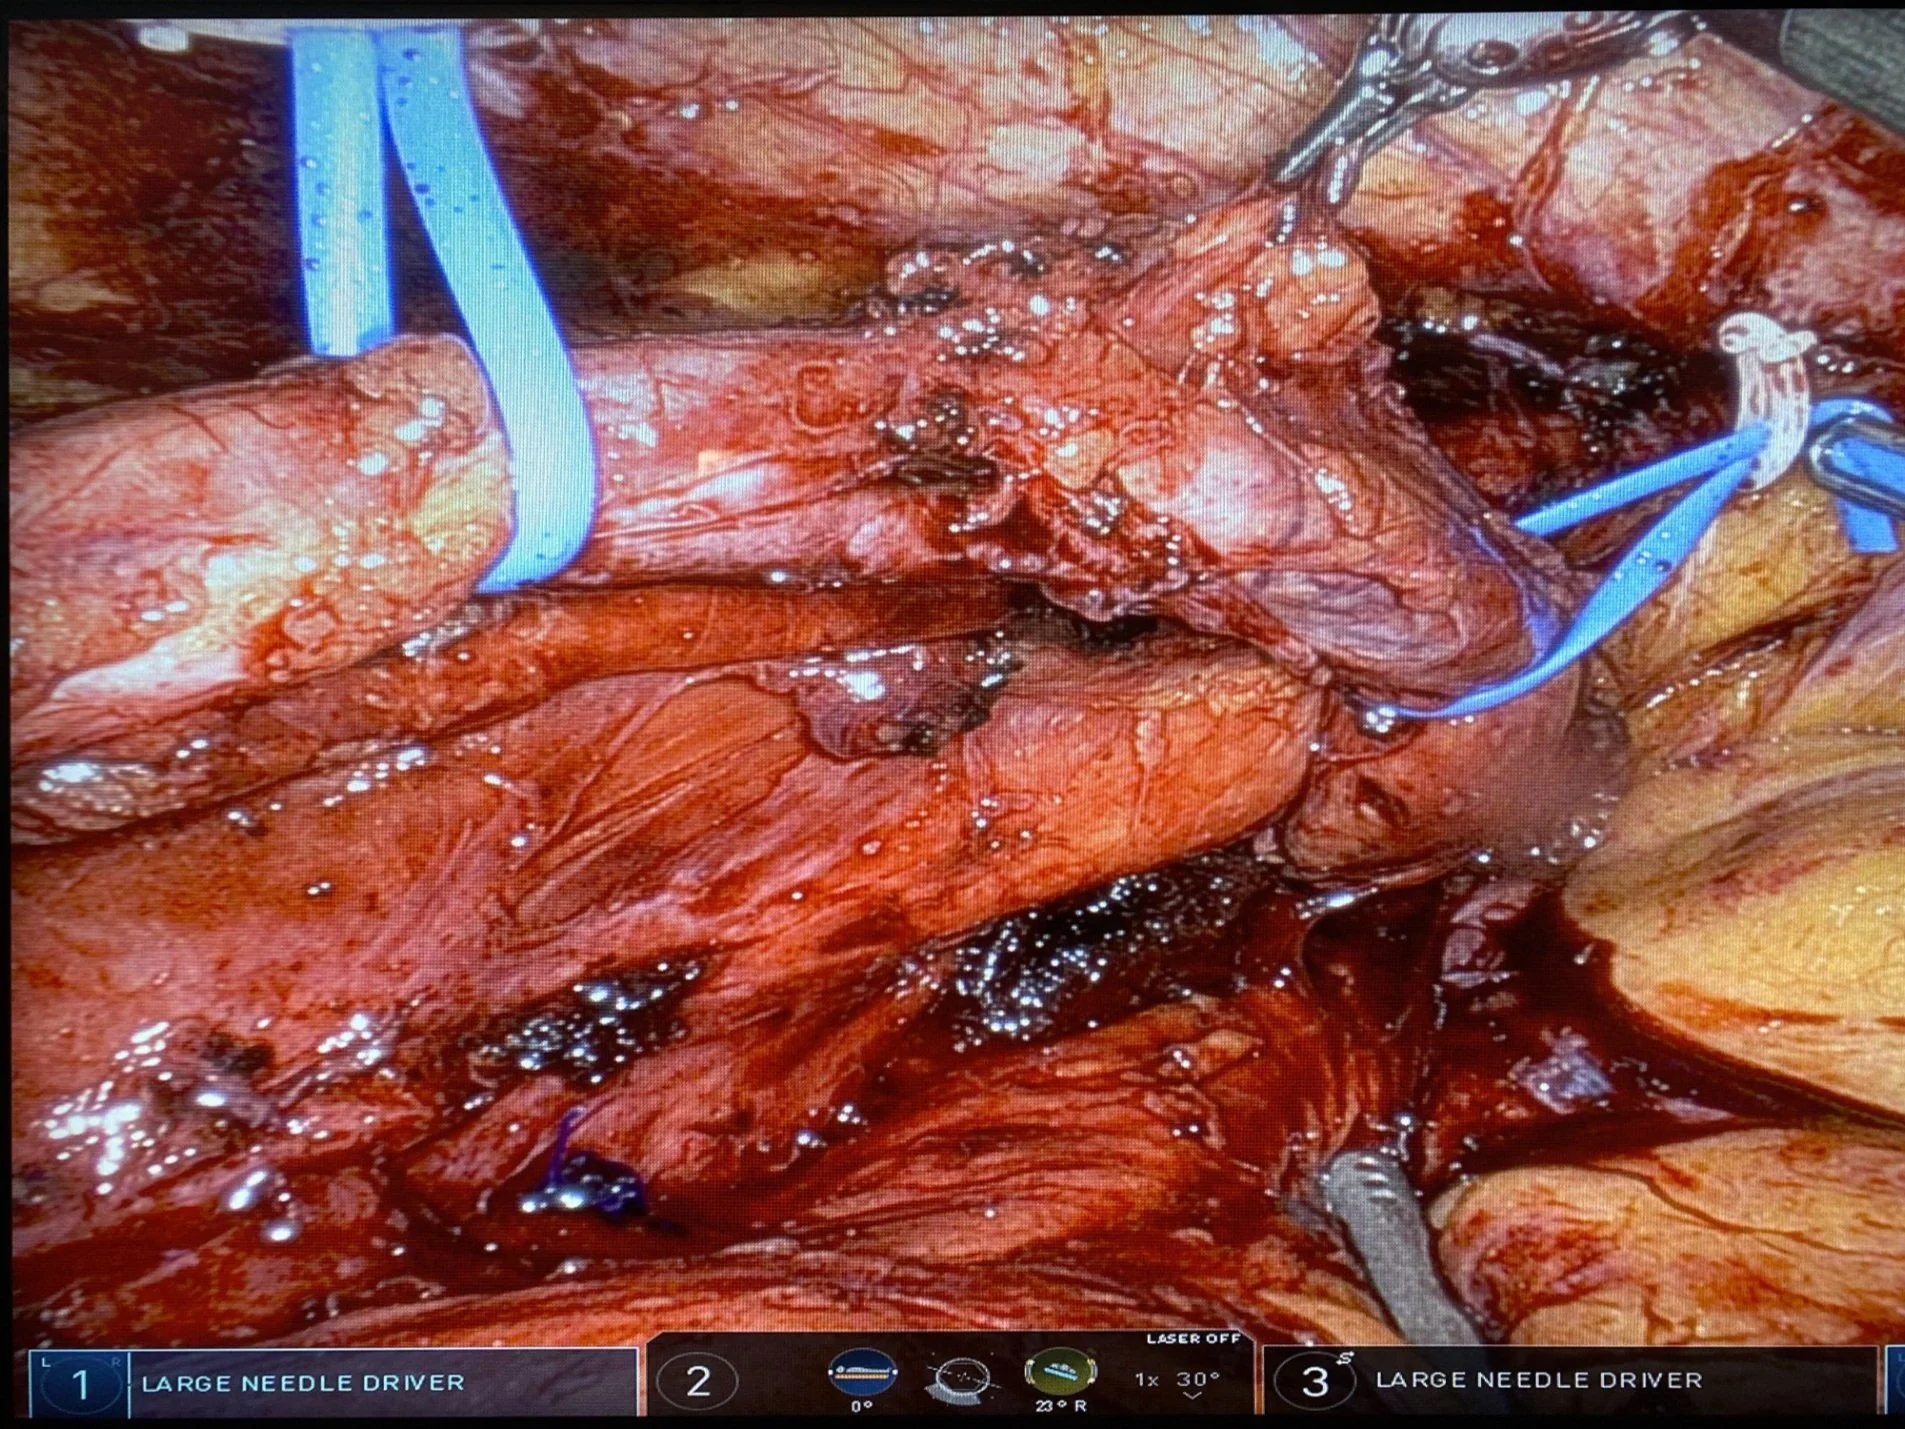

This patient of mine had prior spine surgery. The ureter was unknowingly blocked when the surgeon was dealing with bleeding. Here, during robotic surgery, I identified the ureter and traced it down to the site of blockage….

Getting closer to the actual blockage, I found where the the ureter was sewn to a blood vessel with suture - the purple thread…..

Within the scar tissue, I found a needle left behind during the prior surgery. I performed a robotic ureteroureterostomy repair that fixed the blockage.